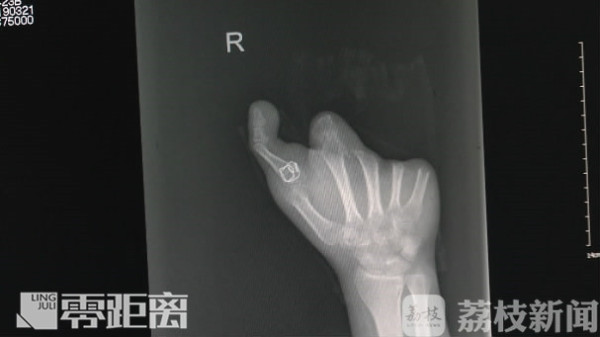

但右手对小刘今后的生活、事业非常重要,如何恢复右手的功能,就成为摆在医生面前的一道难题。经过反复研究,医生们决定取小刘的一根脚趾来再造拇指。这样的情况极为罕见,手术风险也极大,但考虑到患者的强烈愿望,医生们决定冒险一试。

南京医科大学邦德骨科医院手足外科主任江起庭表示,这例手术压力非常大,因为再造手术毕竟不多见,也不多。因为再造跟断指再植不一样,取脚趾头再造的话,如果术后失败坏死,病人家属是没法接受的,所以这例手术再造指对我们要求是百分之百要成功。

经过6个小时的手术,小刘的右手拇指被成功再造。经过两周的康复,小刘再造的大拇指已经可以自由活动,完成抓捏的简单动作,这也燃起了小刘继续从事厨师行业的希望。